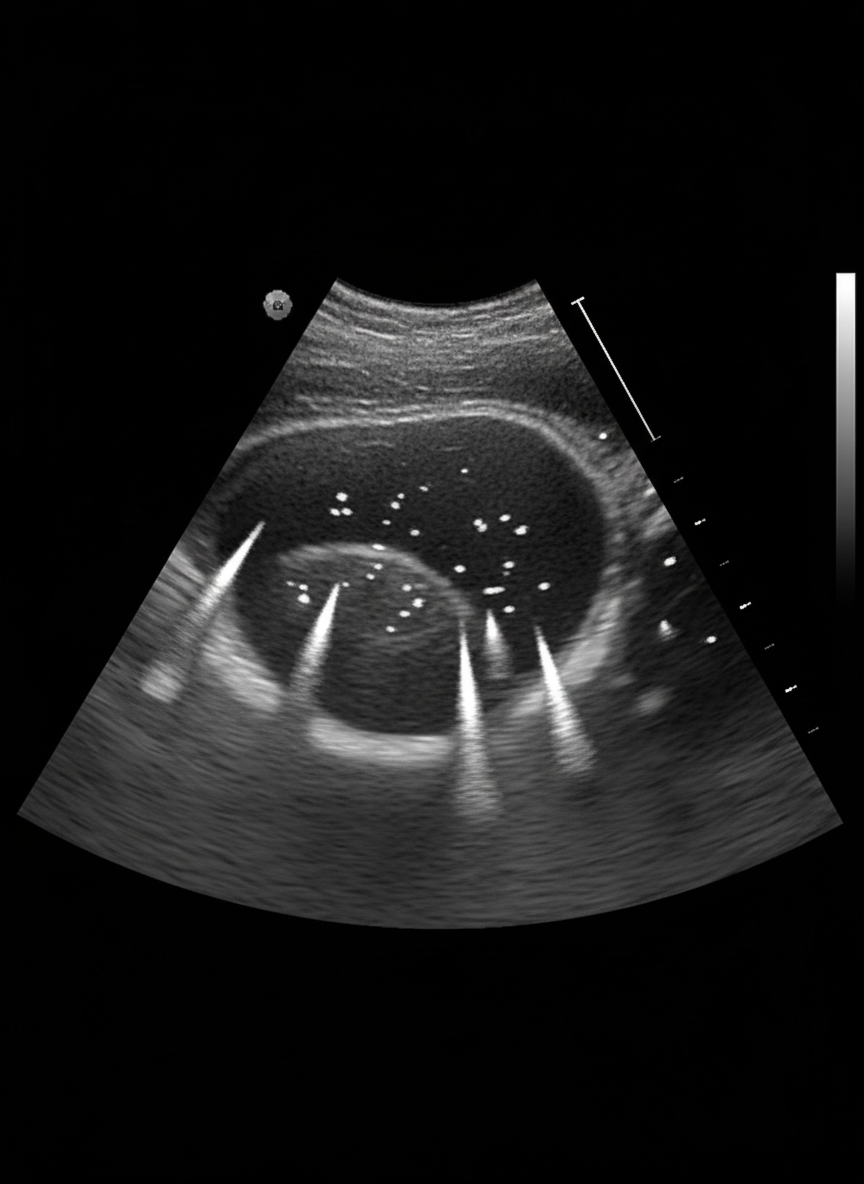

An incidental finding on ultrasound abdomen is suggestive of which of the following?

Explanation: ***Adenomyomatosis*** - Characteristic **comet-tail artifacts** on ultrasound due to **Rokitansky-Aschoff sinuses** filled with cholesterol crystals, making it a classic incidental finding. - Shows **focal or diffuse gallbladder wall thickening** with **hyperechoic foci** that create the pathognomonic comet-tail appearance on ultrasound. *Gallbladder stone* - Presents as **mobile hyperechoic structures** with **posterior acoustic shadowing**, not as wall thickening with comet-tail artifacts. - Typically **symptomatic** with biliary colic rather than being an incidental finding, and moves with patient positioning. *Gallbladder polyp* - Appears as **fixed hyperechoic lesions** attached to the gallbladder wall **without posterior shadowing**. - Does not demonstrate the characteristic **comet-tail artifacts** or **Rokitansky-Aschoff sinuses** seen in adenomyomatosis. *Xanthogranulomatous cholecystitis* - Shows **irregular wall thickening** with **hypoechoic intramural nodules** and loss of normal wall layering on ultrasound. - Usually presents with **severe symptoms** and **pericholecystic fluid**, making it less likely to be an incidental finding.